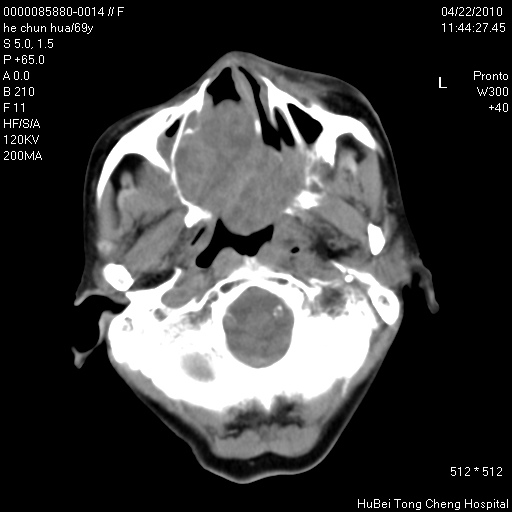

标题: CT25937:女,69Y

硬腭部包块十余年,渐进性增大。

病程长,考虑巨细胞修复性肉芽肿可能性大;

鉴别:神经源性病变、硬结病等。

五楼说得有道理,支持一下。巨细胞修复性肉芽肿好象是外伤出血后引起的修复性改变,骨质呈溶骨性破坏,但病程呈良性过程。